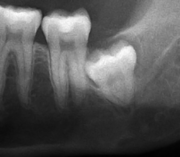

Wisdom teeth likely become impacted because of a mismatch between the size of the teeth and the size of the jaw. Impacted wisdom teeth are classified by their direction of impaction, their depth compared to the biting surface of adjacent teeth and the amount of the tooth's crown that extends through gum tissue or bone. Impacted wisdom teeth can also be classified by the presence or absence of symptoms and disease. Screening for the presence of wisdom teeth often begins in late adolescence when a partially developed tooth may become impacted. Screening commonly includes clinical examination as well as x-rays such as panoramic radiographs.

Impacted wisdom teeth are classified by the direction and depth of impaction, the amount of available space for tooth eruption. and the amount soft tissue or bone (or both) that covers them. The classification structure helps clinicians estimate the risks for impaction, infections and complications associated with wisdom teeth removal.[4] Wisdom teeth are also classified by the presence (or absence) of symptoms and disease.[5]

Impacted wisdom teeth are often described by the direction of their impaction (forward tilting, or mesioangular being the most common), the depth of impaction and the age of the patient as well as other factors such as pre-existing infection or the presence of pathology.[3]:143–144 Of these predictors, age correlates best with extraction difficulty and complications during wisdom teeth removal[6] rather than the orientation of the impaction.[7]